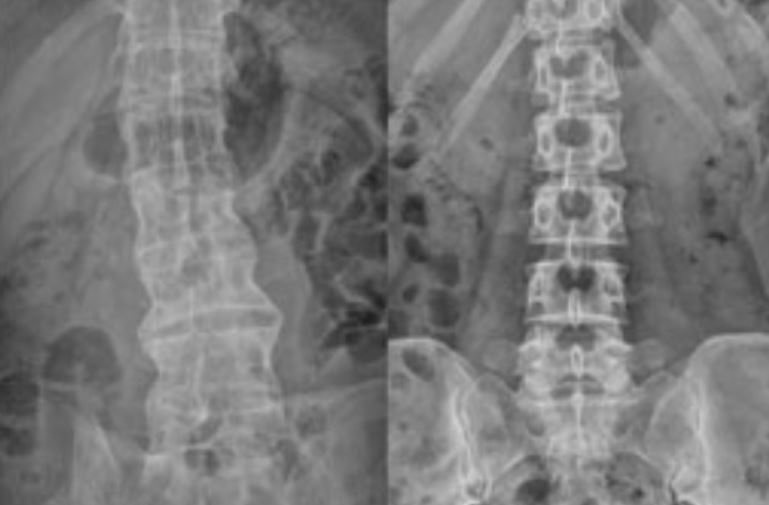

10: Koo BS, Oh JS, Park SY, Shin JH, Ahn GY, Lee S, Joo KB, Kim TH. Tumour

necrosis factor inhibitors slow radiographic progression in patients with

ankylosing spondylitis: 18-year real-world evidence. Ann Rheum Dis. 2020

Oct;79(10):1327-1332. doi: 10.1136/annrheumdis-2019-216741. Epub 2020 Jul 13.

PMID: 32660979.